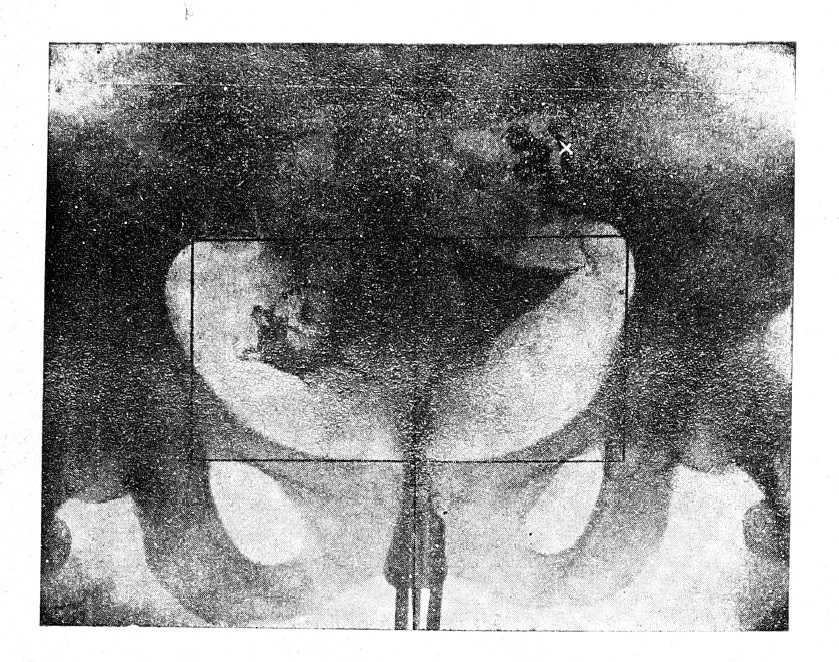

Мы имели возможность выявить интересный факт, связанный с положением яичников. Нами было обращено внимание на то, что в некоторых случаях направление труб указывает на резкое смещение яичников по сравнению с их обычным положением. Этот факт важен, имея в виду наблюдающееся иногда отсутствие эффекта при рентгенотерапии яичников, несмотря на правильную дозировку. Вероятно, мы здесь имеем дело именно с необычным положением яичника, вследствие чего он и не подвергается облучению. В связи с этим можно рекомендовать во всех случаях терапевтического облучения яичников производить предварительную метросальпингографию с целью выявления местоположения яичников или, в крайнем случае, контрольную метросалпингографию в случаях с получением лишь одностороннего эффекта. Для примера мы приводим рентгенограмму-рис. № 4. На ней мы совершенно ясно видим разницу в направлении правой и левой трубы; последняя, извиваясь, направляется резко кверху и медиально, что дает нам возможность сделать заключение о расположении левого яичника в необычном месте. Мы полагаем, что направление центрального луча при рентгенотерапии в данном случае пришлось бы соответствующим образом изменить (см. сечение полей освещения на рис № 4).

Рис. 4. Схематическое изображение полей освещения яичников